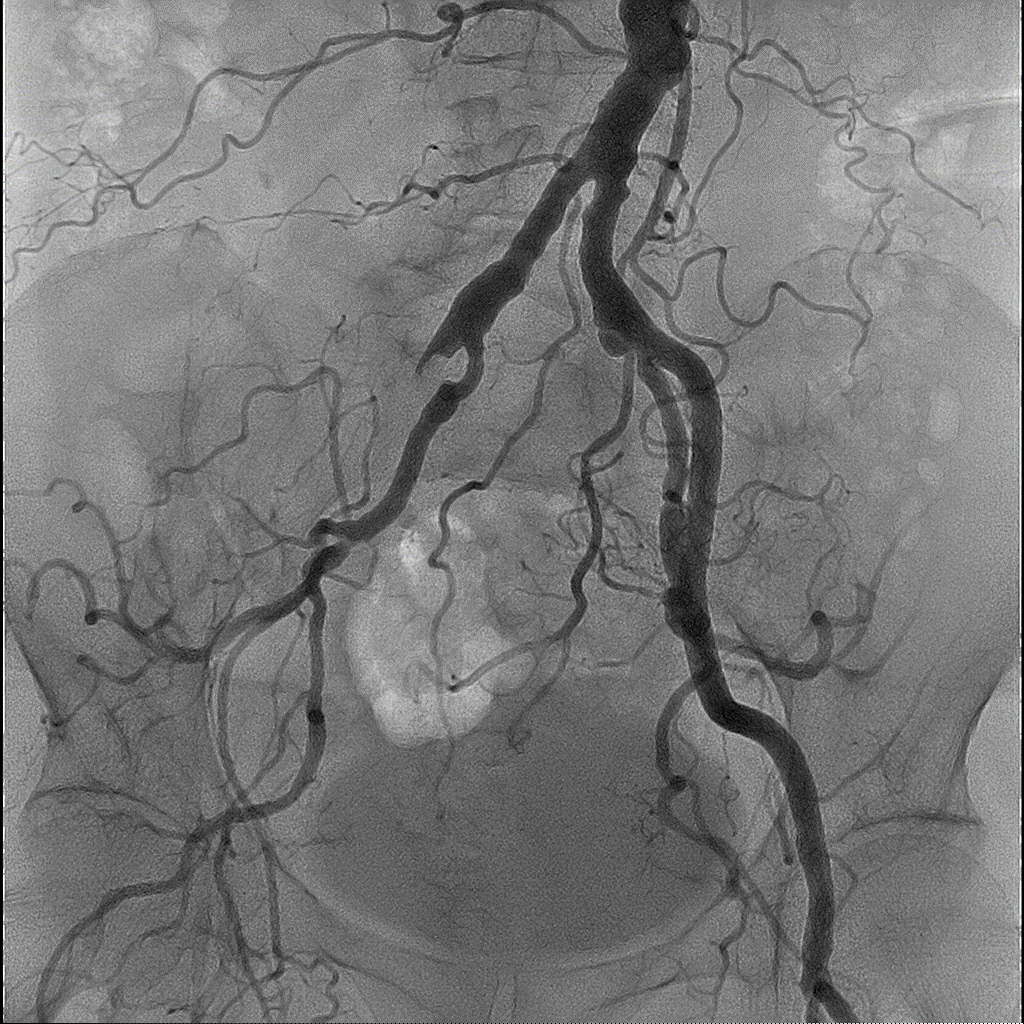

Програмне забезпечення Embolization Plan використовується для аналізу 3D-зображень. Це дозволяє виокремити пухлину і судини, що кровопостачають її, та візуалізувати для процедури трансрадіальної хіміоемболізації (TACE):